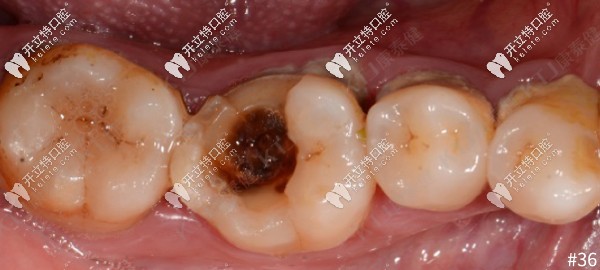

牙齒大面積缺損,用康泰健格萊美瓷嵌體修復(fù)案例分享

牙齒缺失牙齒修復(fù)牙齒嵌體修復(fù)發(fā)布時(shí)間: 2025-05-11

傳統(tǒng)的補(bǔ)牙是把齲壞的部分磨掉,補(bǔ)上材料完成的。但對(duì)于大面積缺損只是簡(jiǎn)單普通補(bǔ)牙并不能達(dá)到好的效果,今天來看一例康泰健格萊美瓷嵌體對(duì)大面積牙齒缺損的修復(fù)案例。